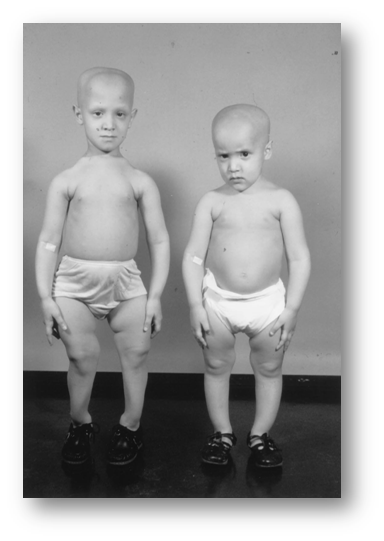

Children with HVDRR and alopecia [Reprinted with permission from J. F. Rosen et al.: J Pediatr 94:729–735, 1979VITAMIN D RECEPTOR AND HVDRR; Endocrine Reviews 20(2):156–188.

- Affected persons demonstrate reduced receptor-binding capacity or defective nuclear internalization of hormone in skin fibroblasts, some also exhibit alopecia totalis.